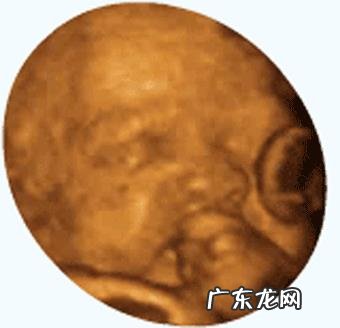

孕6个多月从时间上来看,这是胎动最多最频繁的时候 。

怀孕六个多月,宝宝的胎动厉害是有原因的 。

一:是因为宝宝这时候基本都发育的整齐了 。手脚都发育的完全,可以好好动一动了 。

二:是妈妈的子宫对宝宝来说还相对比较宽敞 。宝宝可以在里面运动自如 。